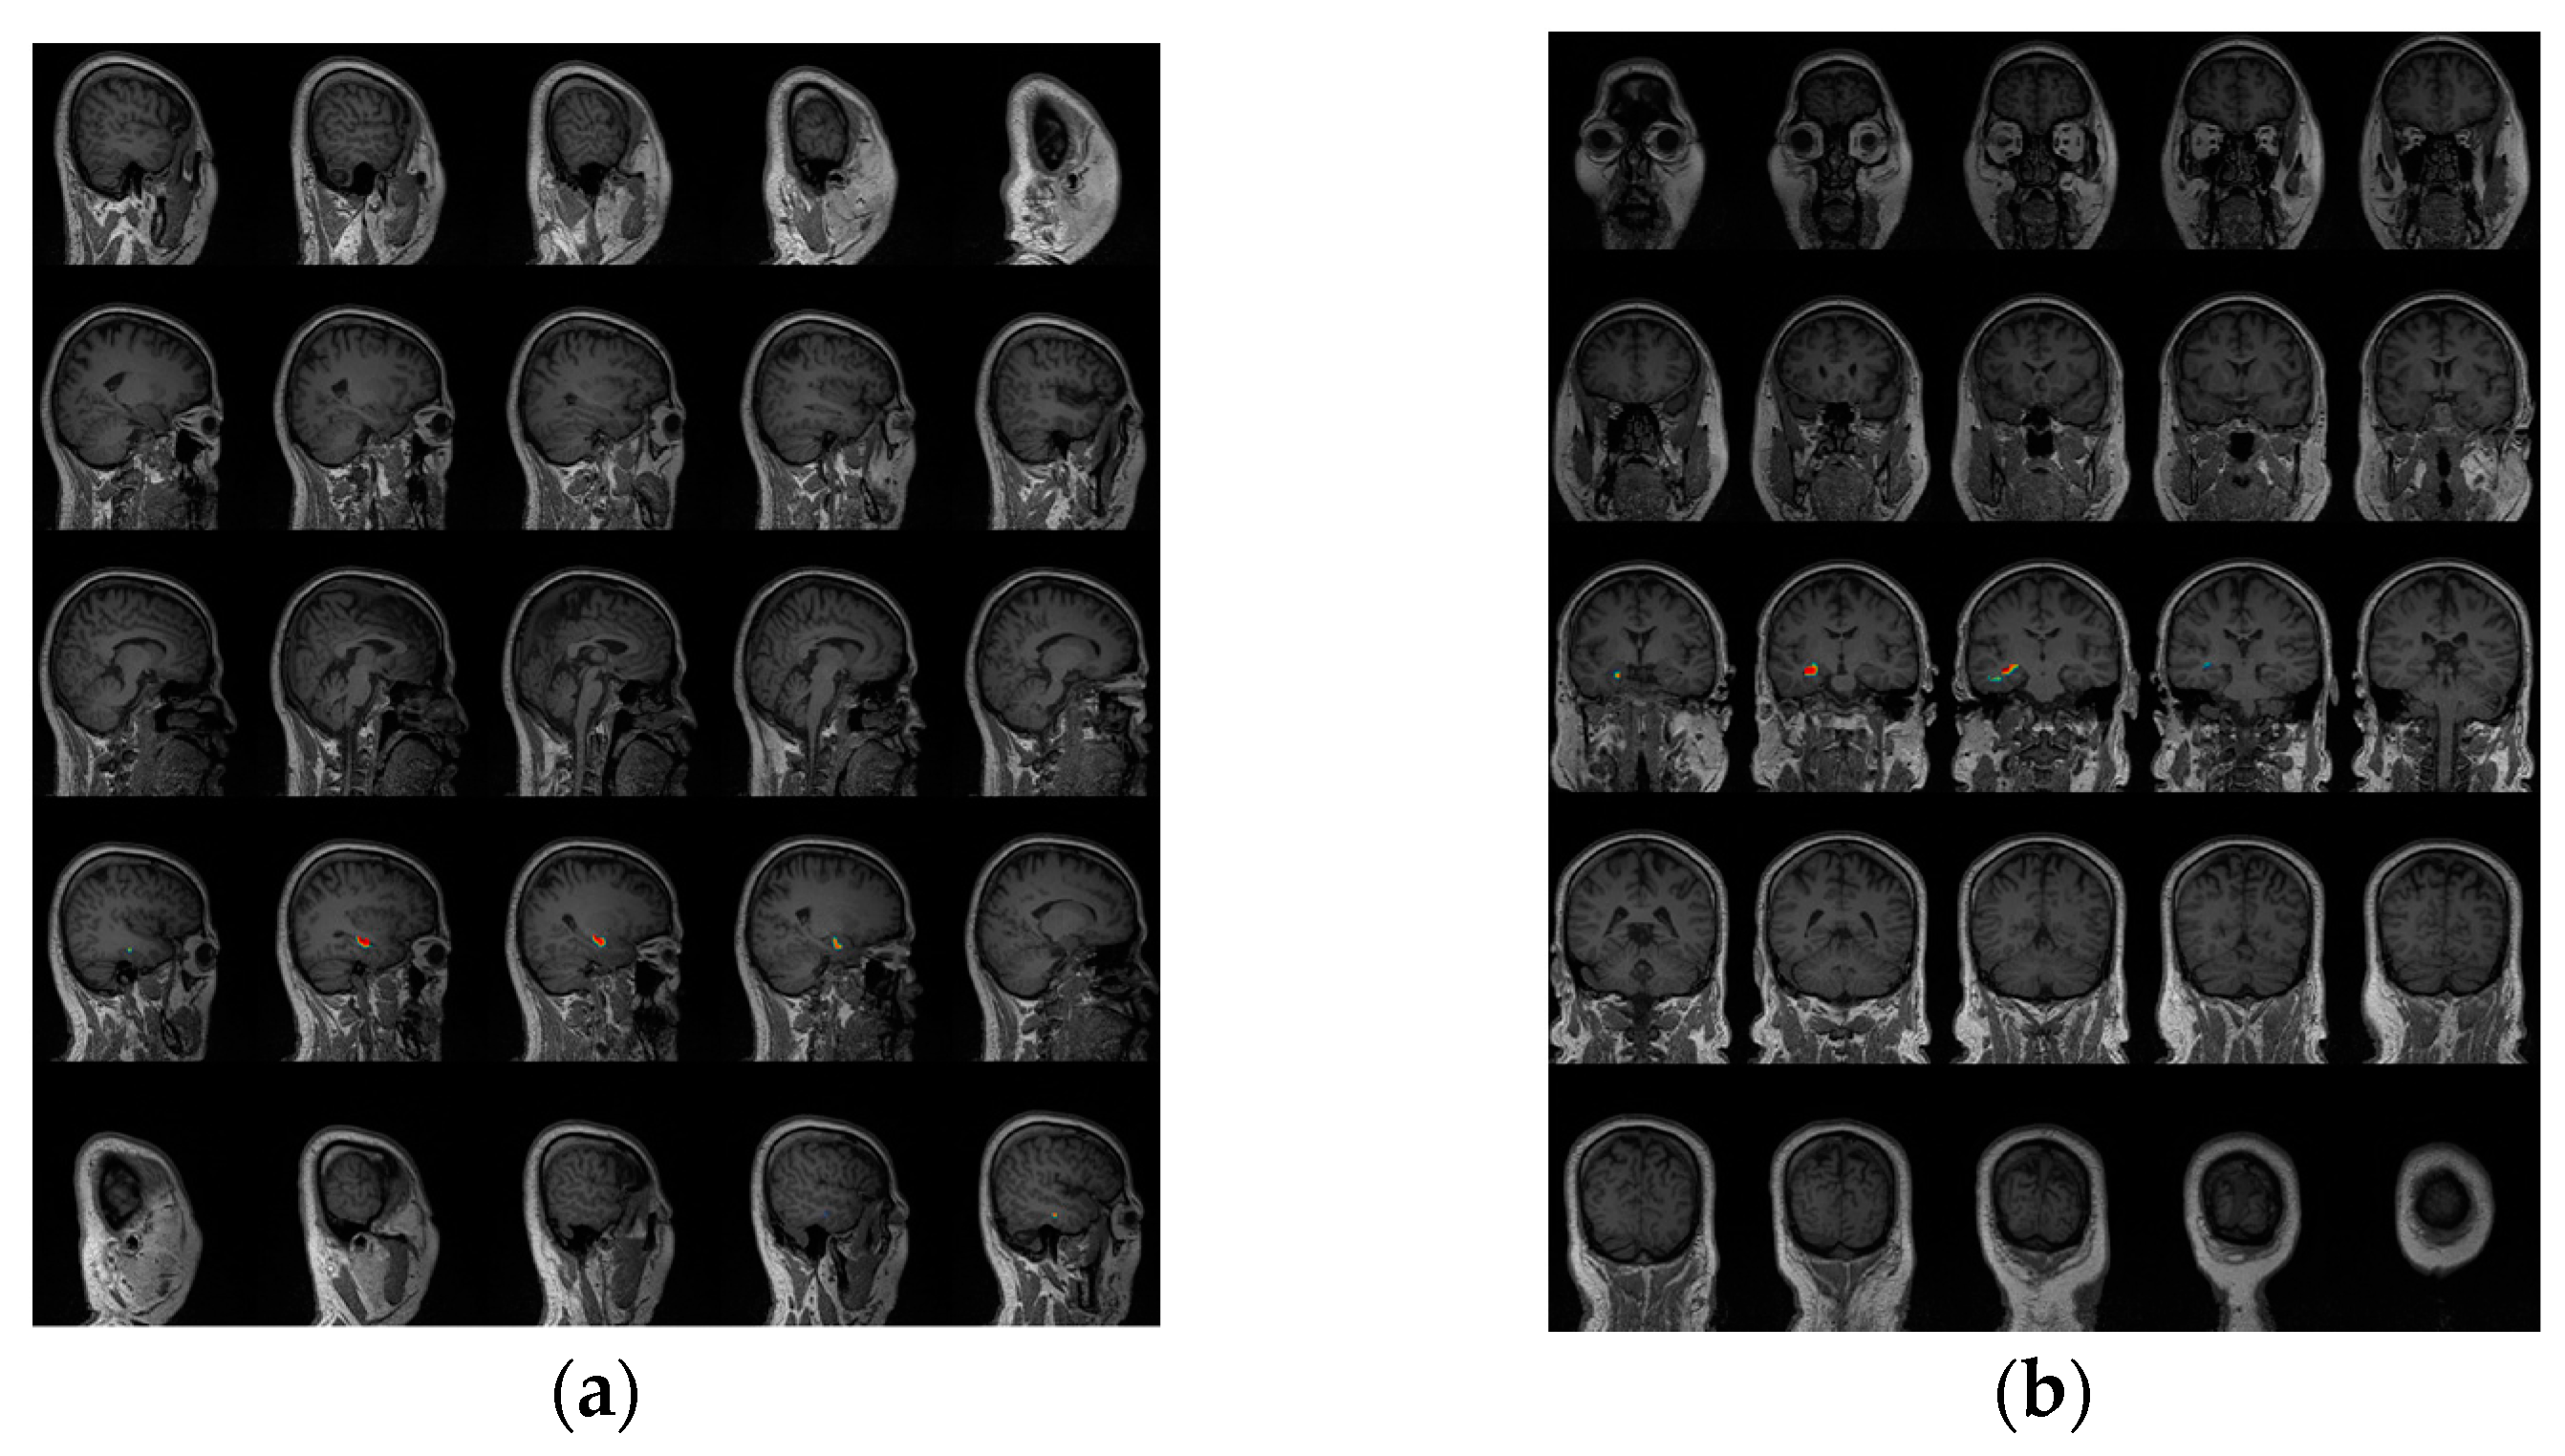

3.3. Epileptogenic Zone Localization Results